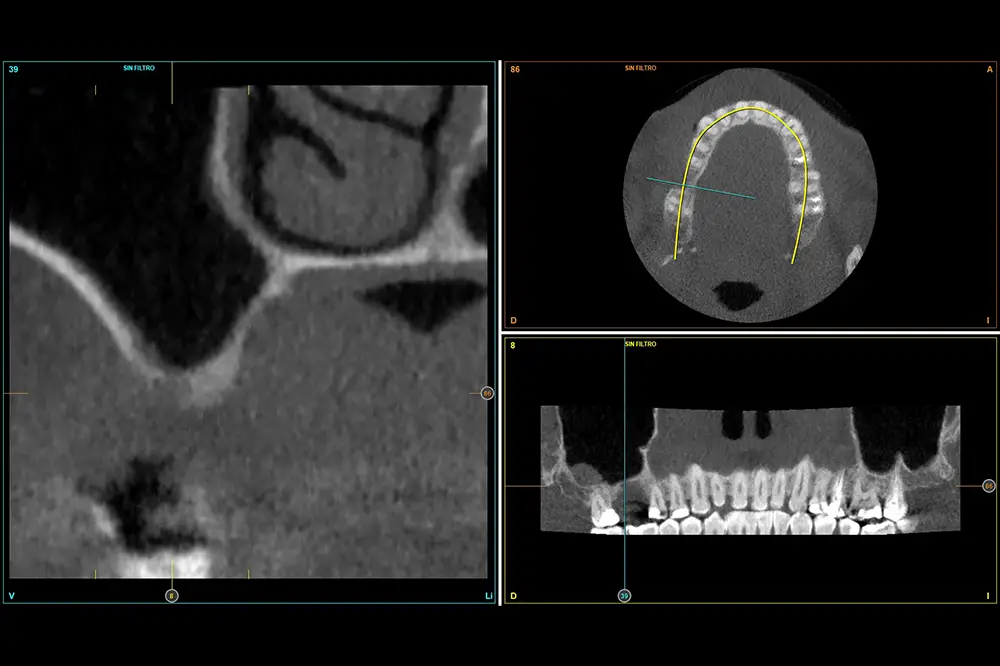

En este caso, la paciente acude con la exodoncia realizada hace dos años de la pieza 16 y una gran atrofia vertical, existiendo únicamente 1 mm en algunas zonas de la cresta, como el área más vestibular, y hasta 3 en la zona más palatina (fig. 9). Procedemos a la realización del fresado tal como se ha descrito en el caso anterior y colocamos el mismo tipo de injerto (autólogo y PRGF- Endoret) y un implante de 4,5 mm de longitud (fig. 10 y 11). Tras la cicatrización a los 4 meses, observamos el aspecto de la zona de la colocación del implante, donde tenemos ahora una altura de 7 mm (fig. 12).

Fig. 9. Cone-beam de planificación donde observamos la escasa altura residual de la cresta a nivel de la pieza 16.

Fig. 12. Estado de la zona una vez consolidado el injerto a los 4 meses.